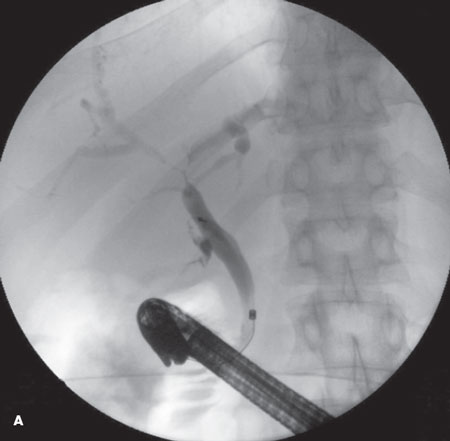

Achalasia

Christopher Knudsen, DO; Terry J. Hundley, MD; Gregory W. Rutecki, MD

<div id="article-content-body"><p><img src="/sites/default/files/images/Achalasia_April_2011_figA%26B.jpg" style="float: left; margin-left: 8px; margin-right: 8px;...